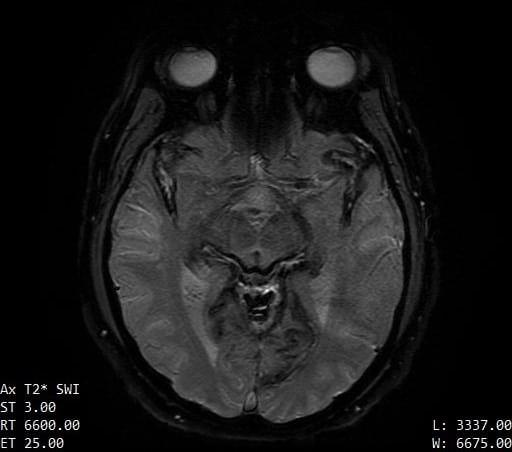

The contours of the cerebrum, cerebellum, and brainstem are outlined with a T2 hypointense signal with blooming on susceptibility weighted sequences, which is compatible with the clinical history of superficial siderosis. A majority of the T2 hypointense signal is present in the superior folia of the cerebellum but also seen coating the surfaces of the brainstem, the cortical surfaces along the Sylvian fissures, and the cortical surfaces of the paramedian sulci of the frontal and occipital lobes. Few subcortical and periventricular T2/FLAIR hyperintensities are present in both cerebral hemispheres.²

If you look at each image, you can see the dark areas where his hemosiderin deposits are. The radiologist will use the same machine and settings, so we should visually compare the new images with these for some positive change.³